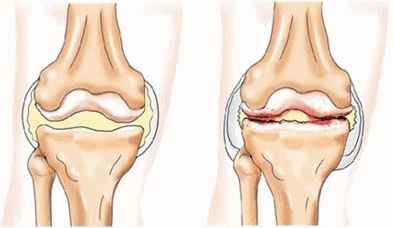

Все кости человека соединены посредством суставов, связок и сухожилий.

При систематических занятиях физическими упражнениями и спортом суставы развиваются и укрепляются, повышается эластичность связок и мышечных сухожилий, увеличивается гибкость. И, наоборот, при отсутствии движений разрыхляется суставной хрящ и изменяются суставные поверхности, сочленяющие кости, появляются болевые ощущения, возникают воспалительные процессы.

Движение осуществляется с помощью сустава, в котором соединяются две кости. Суставы

— подвижные соединения, область соприкосновения костей в которых покрыта суставной сумкой из плотной соединительной ткани. Суставная жидкость уменьшает трение между поверхностями при движении, эту же функцию выполняет и гладкий хрящ, покрывающий суставные поверхности.

Суставная капсула прочно соединяется со связками

— плотными волокнистыми структурами, соединяющими две кости. Они помогают стабилизировать сустав и предотвращают неестественные движения, позволяя в то же время совершать движения в нормальных условиях.

Главная функция суставов — участвовать в осуществлении движений. Они выполняют роль демпферов, гасящих инерцию движения и позволяющих мгновенно останавливаться в процессе движения.